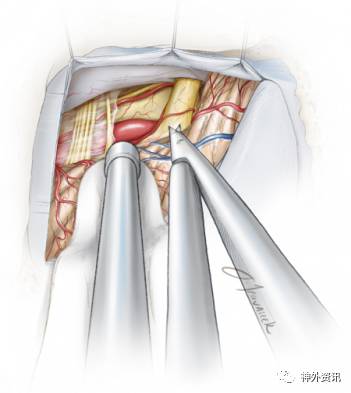

图15. 血管神经冲突会导致面神经REZ区发生褪色而向灰色改变。冲突处位于VIII神经入脑干处的下方(颜色更加白),用剥离子轻轻牵拉开VIII神经后就可看到面神经REZ区。责任血管(一般是小脑前下或后下动脉)就在VII神经的腋部,抬起血管,将血管与神经分离后即可垫入Teflon。

在操作过程中要注意保护责任血管的分支。要注意的是血管神经冲突处位置深在,紧临脑干。在探查时,这一区域必须充分松解蛛网膜,并以合适的角度动态地牵拉小脑。

图16. 上图显示的是REZ区由于临近责任血管袢压迫造成的褪色区域(黑色箭头)。下图显示的是垫入Teflon之后的情况。请注意观察覆盖在VIII神经表面的罂粟碱浸泡的明胶海绵(黄色箭头)。

图17. 责任血管与面神经REZ区域及脑干相邻全程均要用Teflon垫开。一般移开责任血管后LSR波就会消失。尽管不是百分之百确定,但是LSR波的消失意味着病变区域已经找到并妥善处理好。

笔者将撕碎的Teflon放置在责任血管与脑干之间,而不鼓励放置一整块Teflon,因为它的位置在术后可能会改变。将这些Teflon棉片向上和向下(如插图所示)推,将血管与神经全程垫开,远离脑干。

图18. 图中显示责任血管已经被垫开。需要关注的是始终要注意血管神经冲突处一般都位于靠近脑干的REZ区域,而非仅仅是面神经的脑池段。